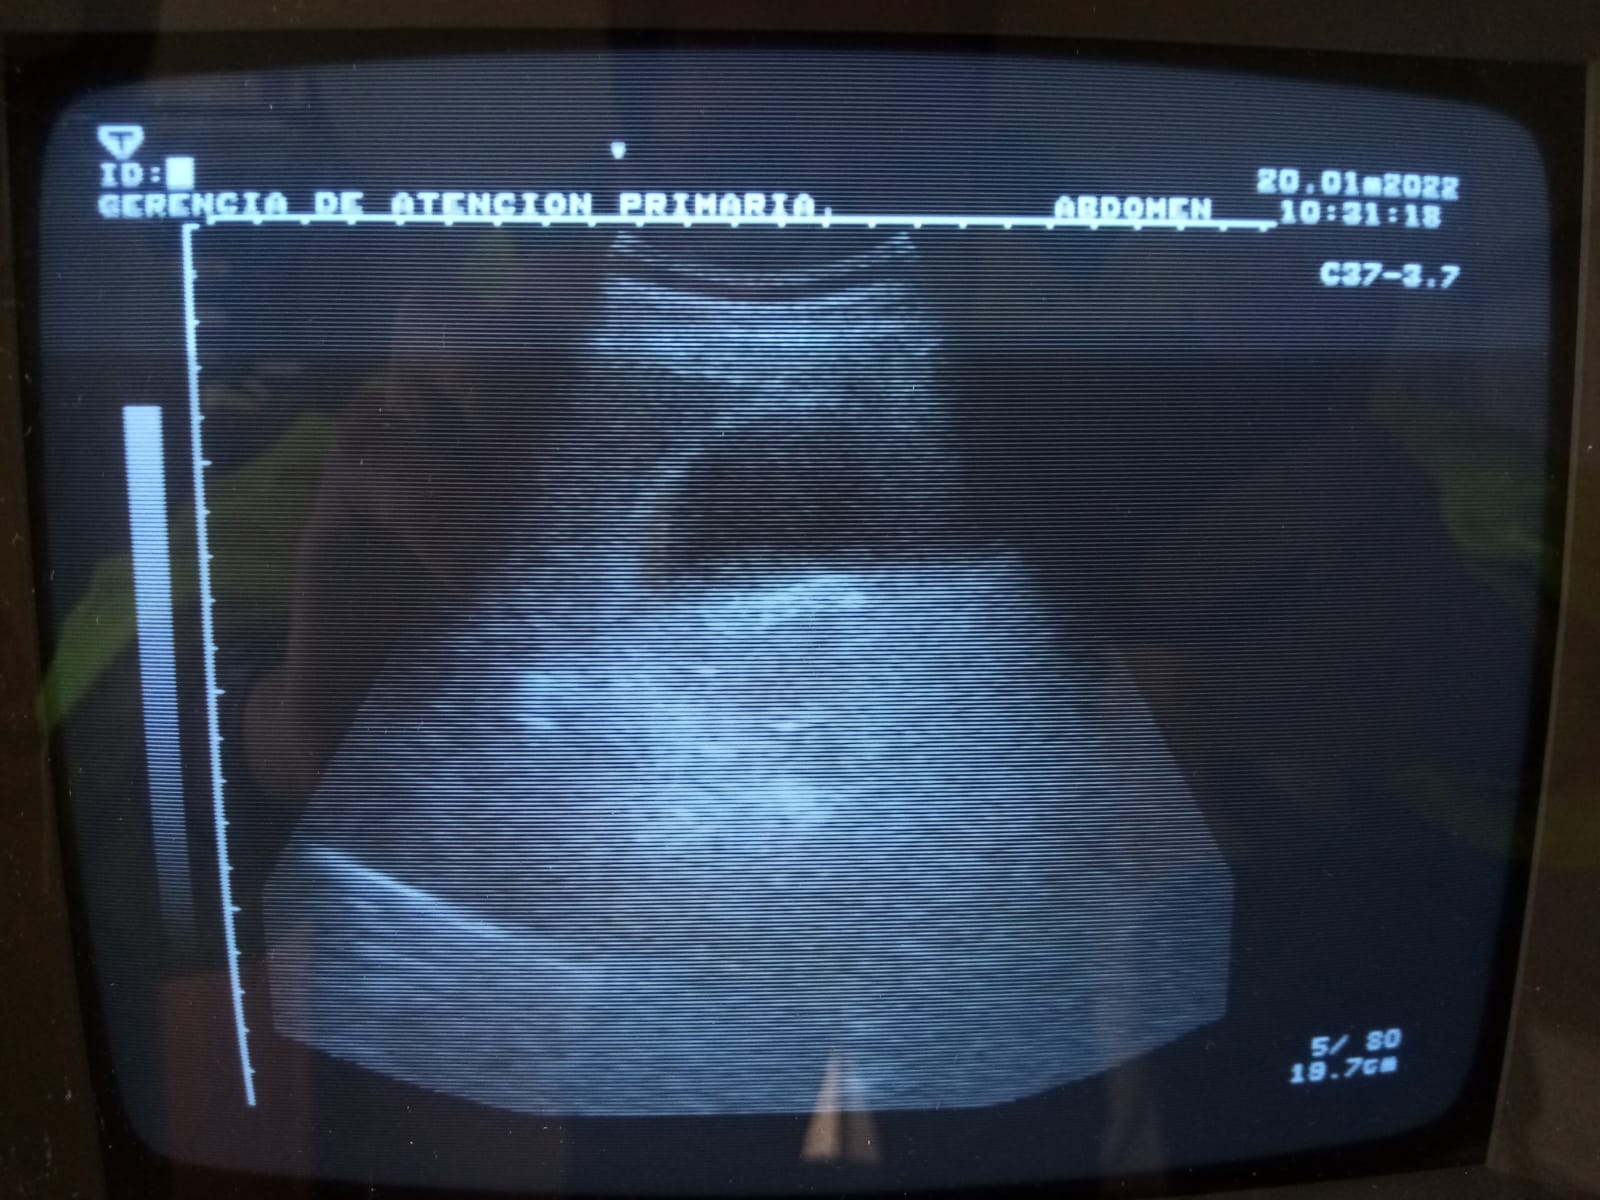

Vesícula biliar de tamaño conservado (38,5 mm), pared engrosada (6,7 mm), contenido biliar significativo, alitiásica.